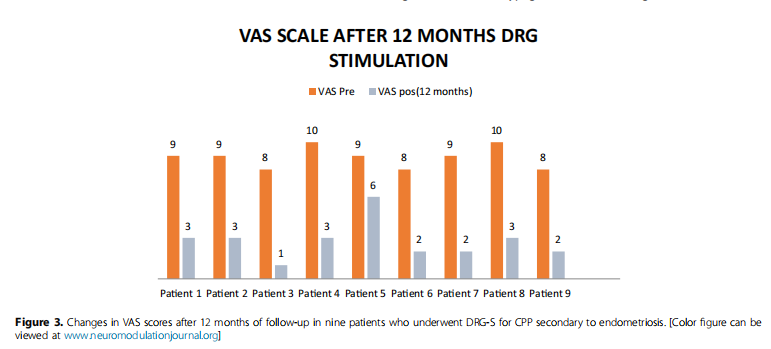

十名患者因子宫内膜异位症引发的慢性盆腔疼痛(CPP),接受了双侧L1和S2背根神经节刺激(DRG-S)的试验性治疗。经过四至七天的试验期,九名患者符合标准,继续进行了永久植入手术;而一名患者因试验效果不佳,未能达到研究纳入标准。所有参与研究的患者,在手术前(基线)和手术后12个月,均接受了评估,评估内容包括视觉模拟评分(VAS)、麻醉药物使用情况以及SF-12生活质量调查问卷。在经过12个月的DRG刺激治疗后,9名患者的疼痛评分,如下图所示均有所下降,有效率(VAS评分降低≥50%的比例)为88.9%,表明DRG刺激在治疗此类疼痛方面具有一定的疗效。

患者术后12个月VAS变化